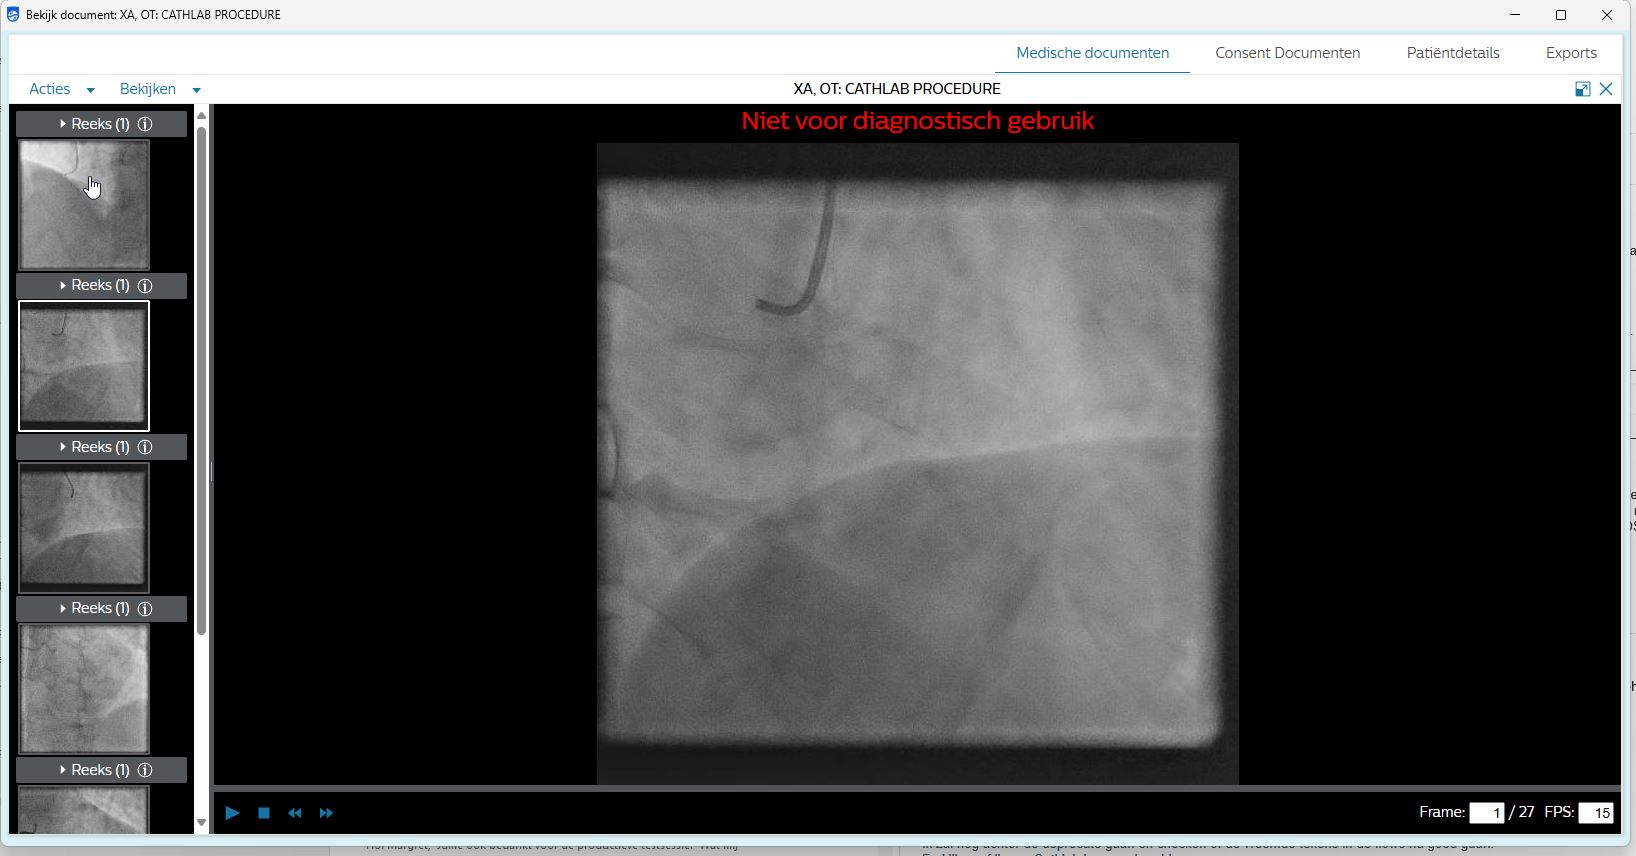

Het Hart-echo (ISCV), het ECG (ELILINK), en het Cath Lab systeem zijn daarvoor aangesloten op het XDSCloud platform van Founda Health.Met deze uitbreiding wordt een grote stap gezet richting een uniforme, specialisme overstijgende aanpak van databeschikbaarheid.

Zowel cardiologiebeelden, als ECG's zijn nu landelijke beschikbaar via een veilige, op internationale standaarden gebaseerde XDS infrastructuur. Hierdoor worden snellere doorverwijzingen binnen regionale netwerken (bijv. UMC Utrecht, Amsterdam UMC), en betere zorgcoördinatie tussen afdelingen en ziekenhuizen mogelijk. Doordat zowel beelden als ECGs automatisch bij de XDSCloud worden aangemeld is er ook minder belasting voor IT- en afdelingsteams.